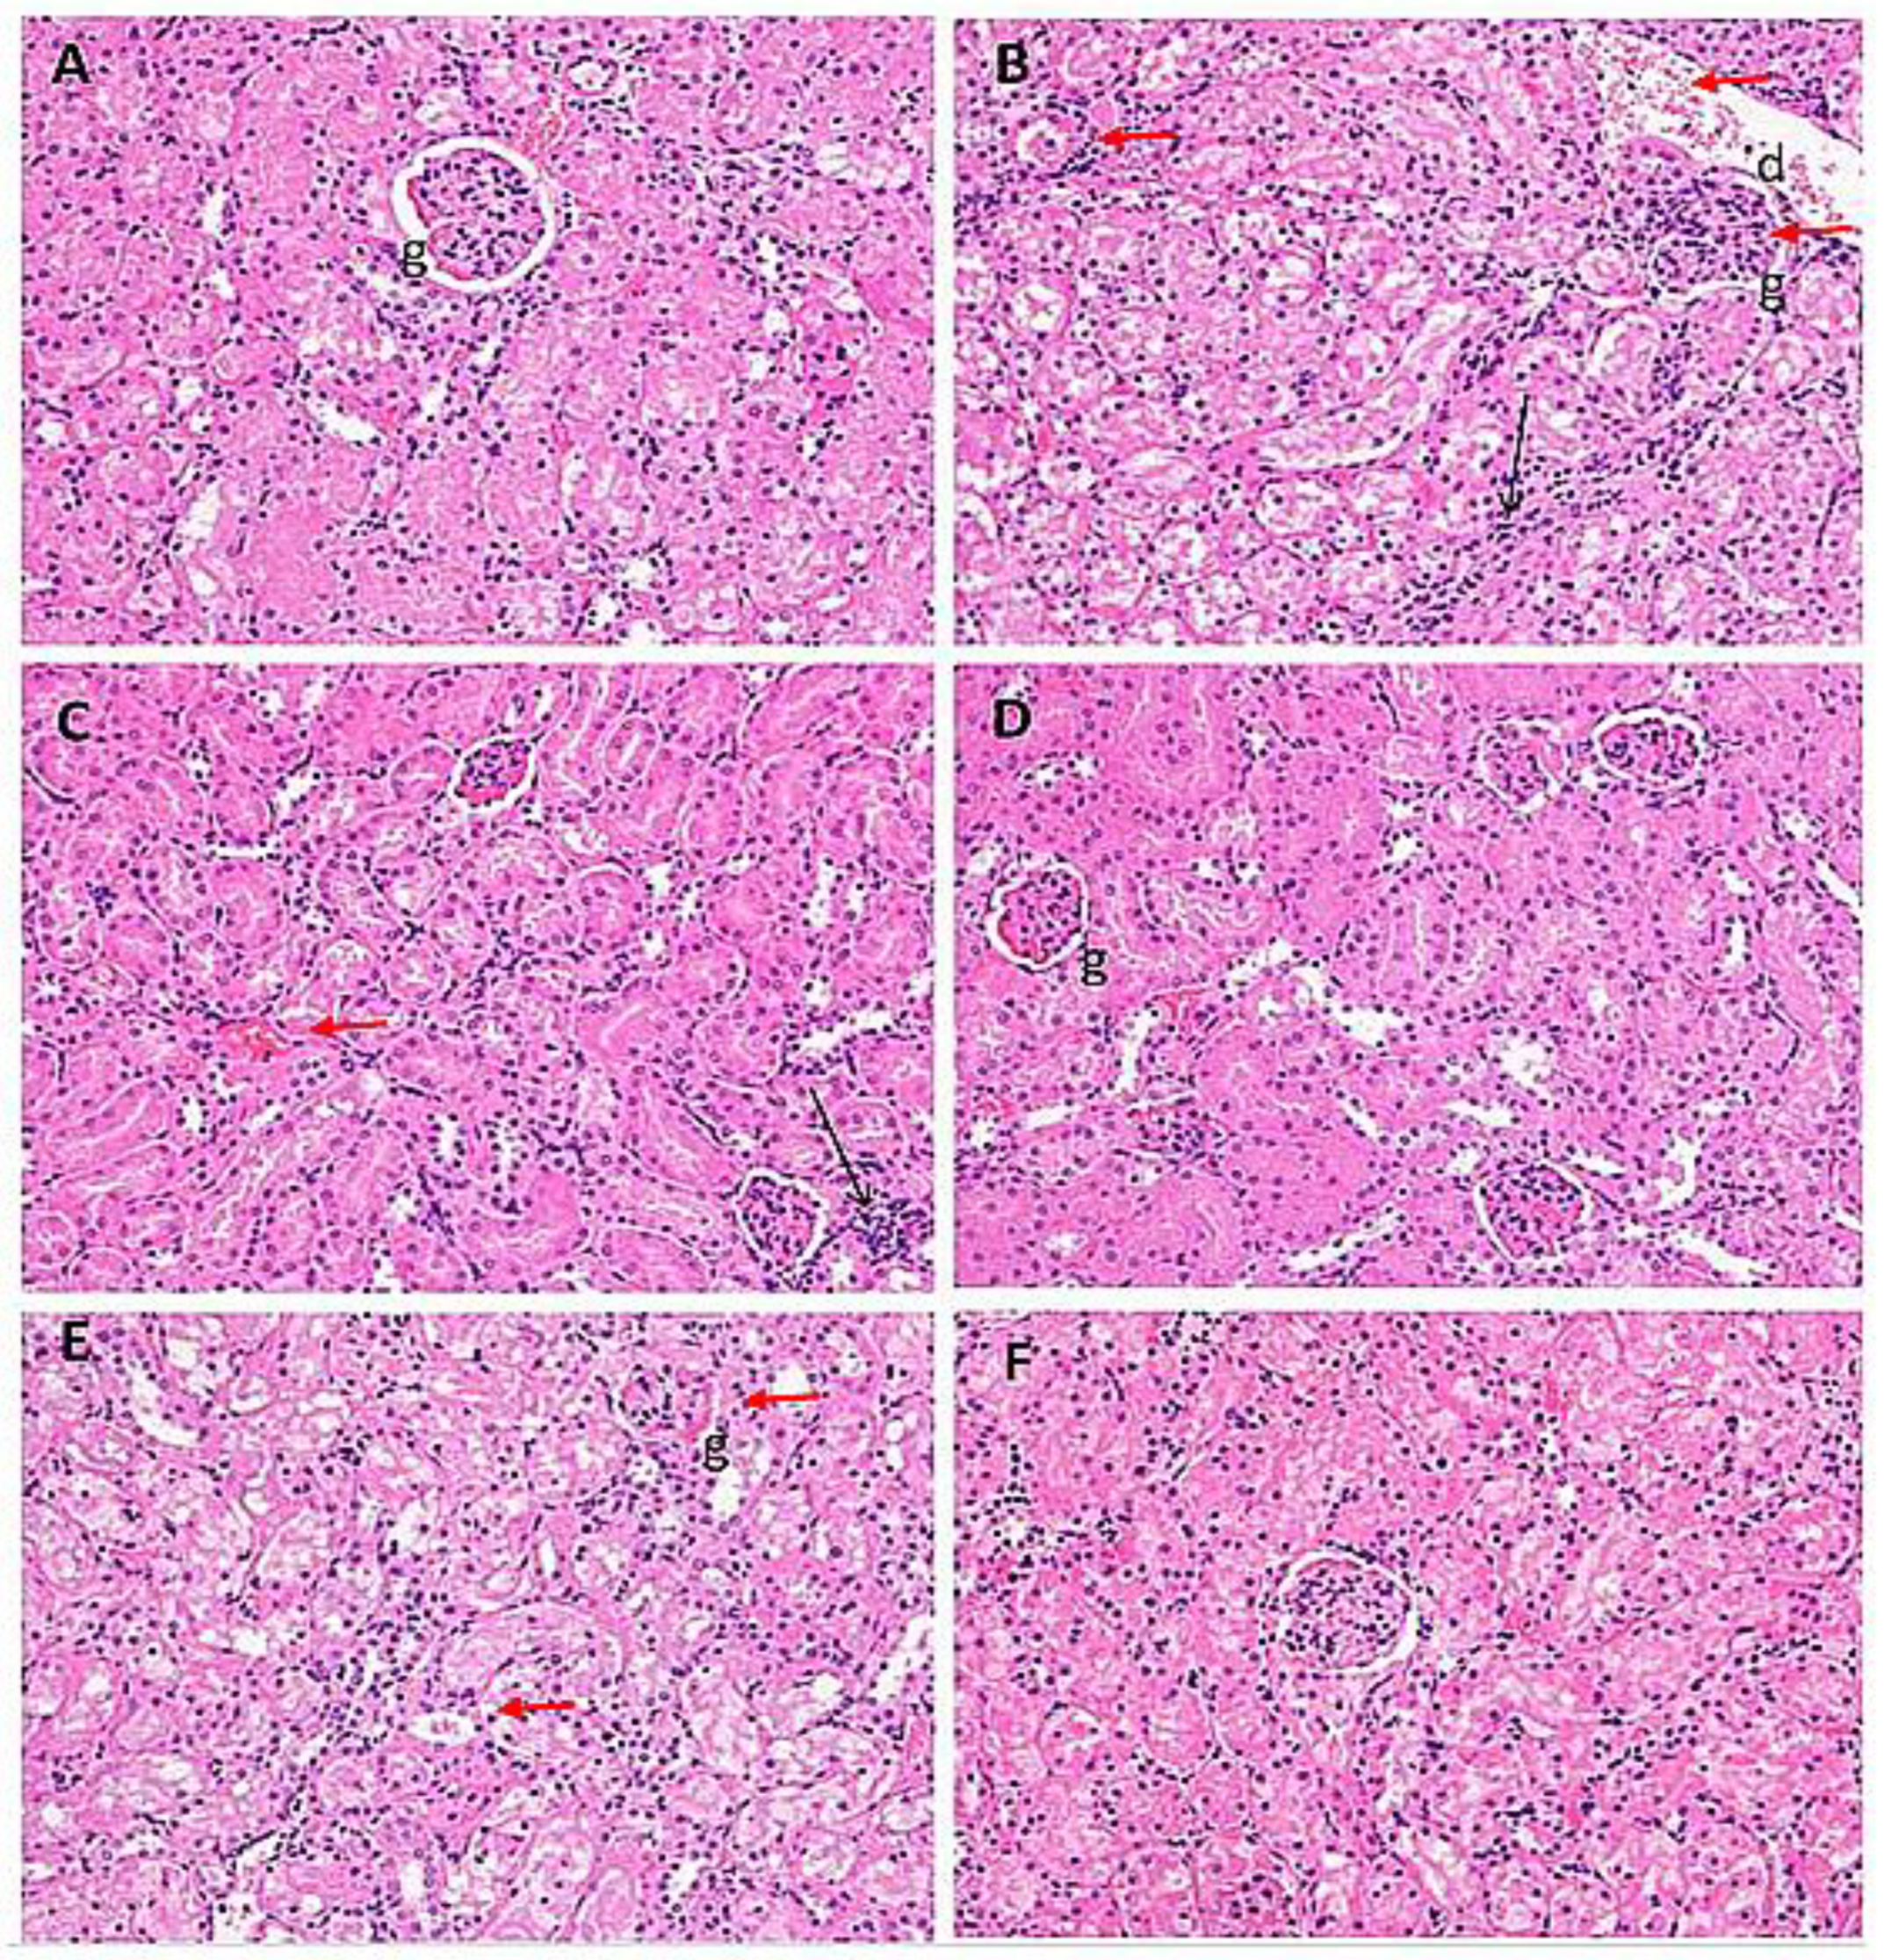

2.7. Histological Evaluation of Kidney Samples

| Treatment Groups | I | II | III | IV | V | VI |

|---|---|---|---|---|---|---|

| Oedematous glomeruli | − | +++ | ++ | − | +++ | − |

| Hemorrhage | − | ++ | ++ | − | − | − |

| Infiltration of inflammatory cells | − | +++ | ++ | + | ++ | + |

| Hyaline casts | − | ++ | ++ | − | ++ | + |

| Disintegrated nucleus | − | + | − | − | − | − |